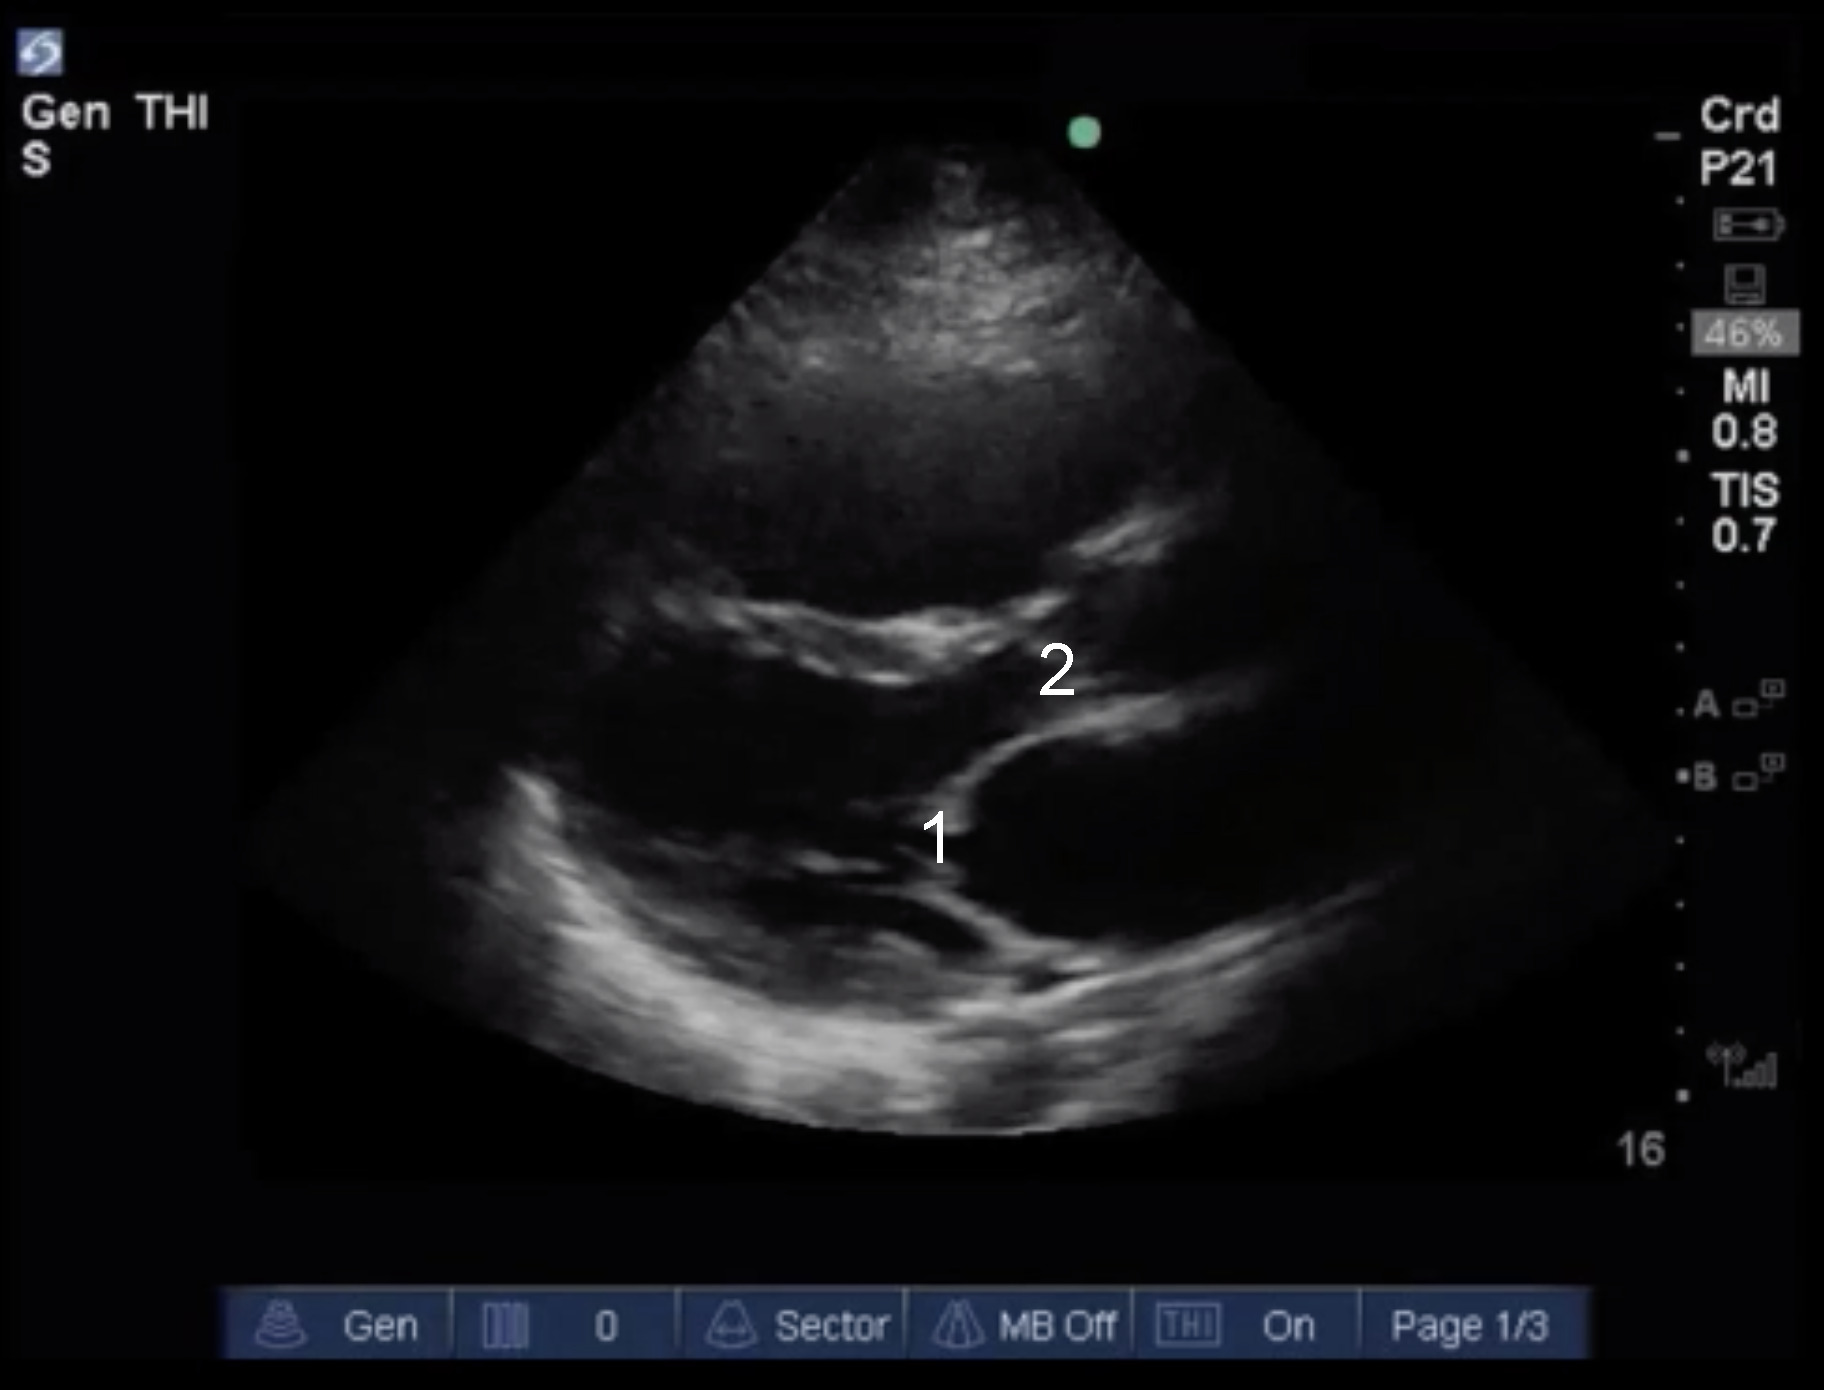

Cardiac 2 Valves Eyeball Assessment Example 3 Image

Mitral Valve

Aortic Valve